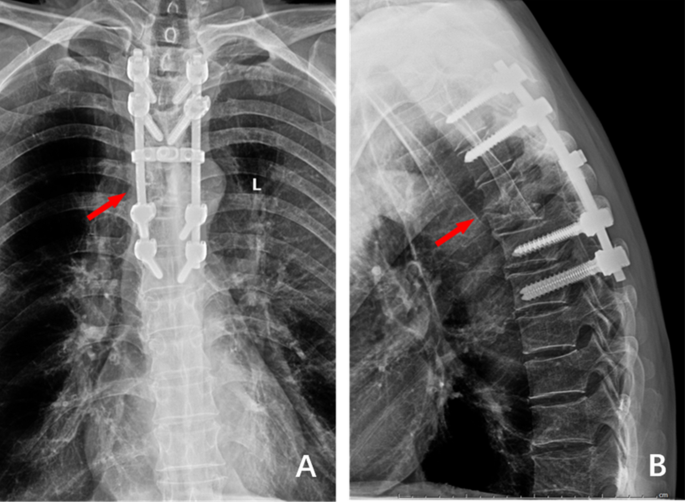

(A) and (B) 1 week after the operation, the frontal and lateral X-ray films showed that the internal fixation position was good, the deformity was corrected well, and The Cobb Angle was 19°.